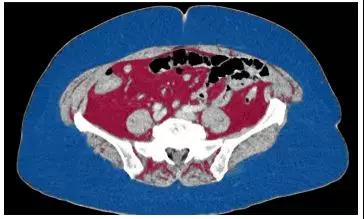

根据圣路易斯华盛顿大学医学院研究人员的一项新研究,腹部脂肪影响肾癌女性存活率,但不影响男性。

研究人员分析了145名男性肾癌和77名女性肾癌患者的影像,结果发现,50%有腹部脂肪的女性肾癌患者在确诊后3年半内死亡,而一半以上腹部脂肪少的肾癌女性在10年后仍然活着。对于男性来说,腹部脂肪的含量对于存活期没有什么区别。

评估身体脂肪的大多数方法都依赖于一个人的身高和体重。但不是所有的脂肪都是一样的。

健康男性与健康女性新陈代谢存在差异,不仅关于脂肪如何运输,而且关于他们的细胞如何使用葡萄糖、脂肪酸和其他营养物质。

研究结果表明,女性肾癌的发展和进展可能不同于男性。体重过重是肾癌发生的主要危险因素,但并不一定预示不良结局。相反,这项新研究表明,诊断后患者存活的时间不仅与总脂肪有关,而且与体脂分布有关,至少对于女性而言是这样的。